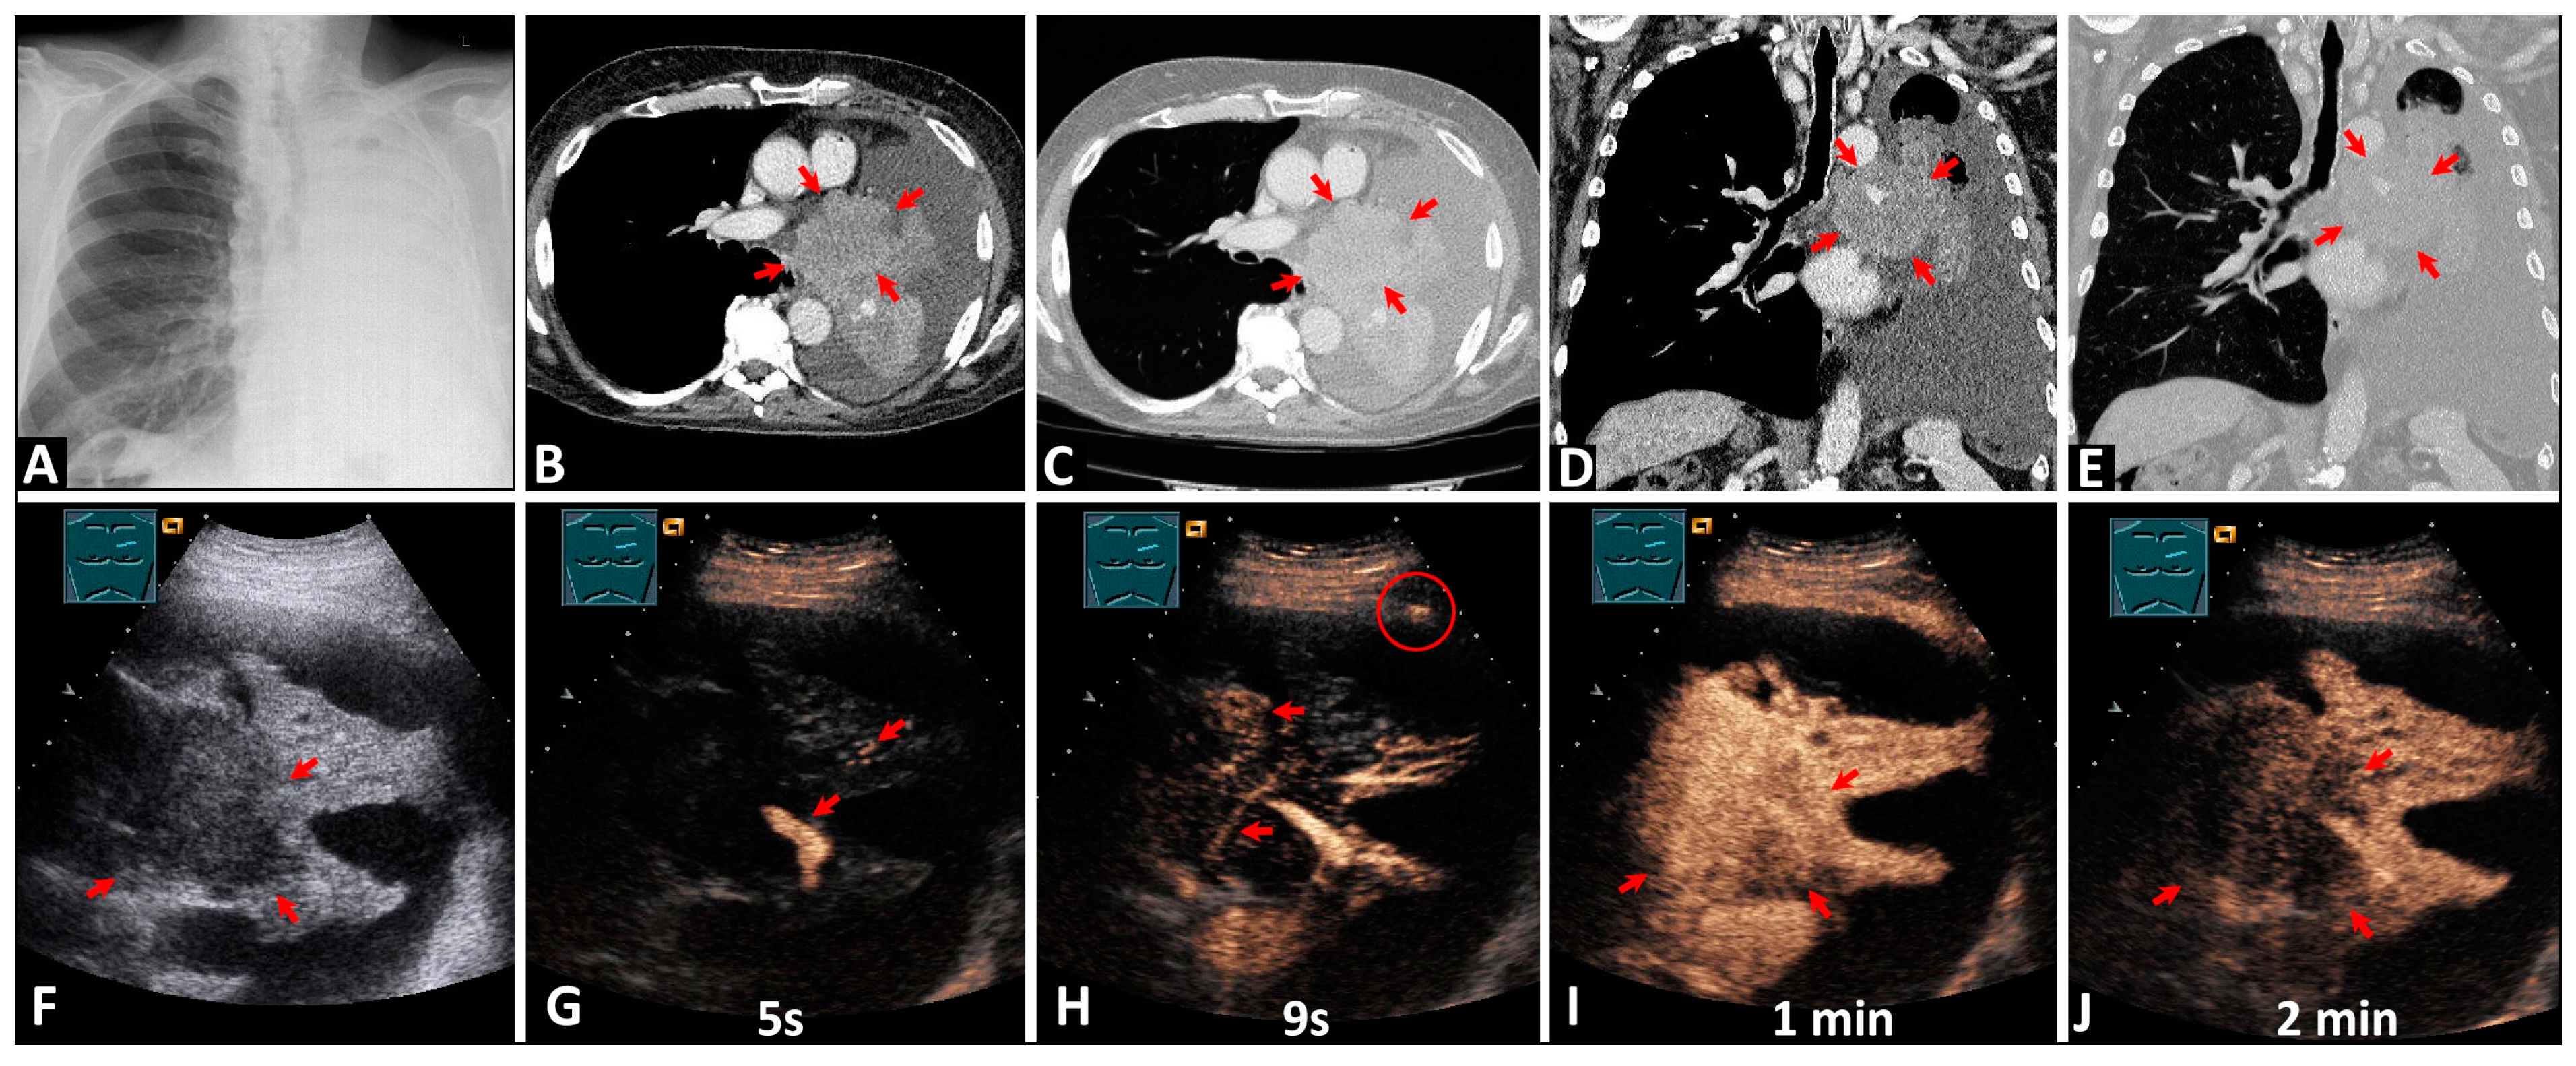

3.2.1. Differentiation between the Tumor and Atelectatic Tissue on B-US

3.3.1. Differentiation between the Tumor and Atelectatic Tissue on CEUS